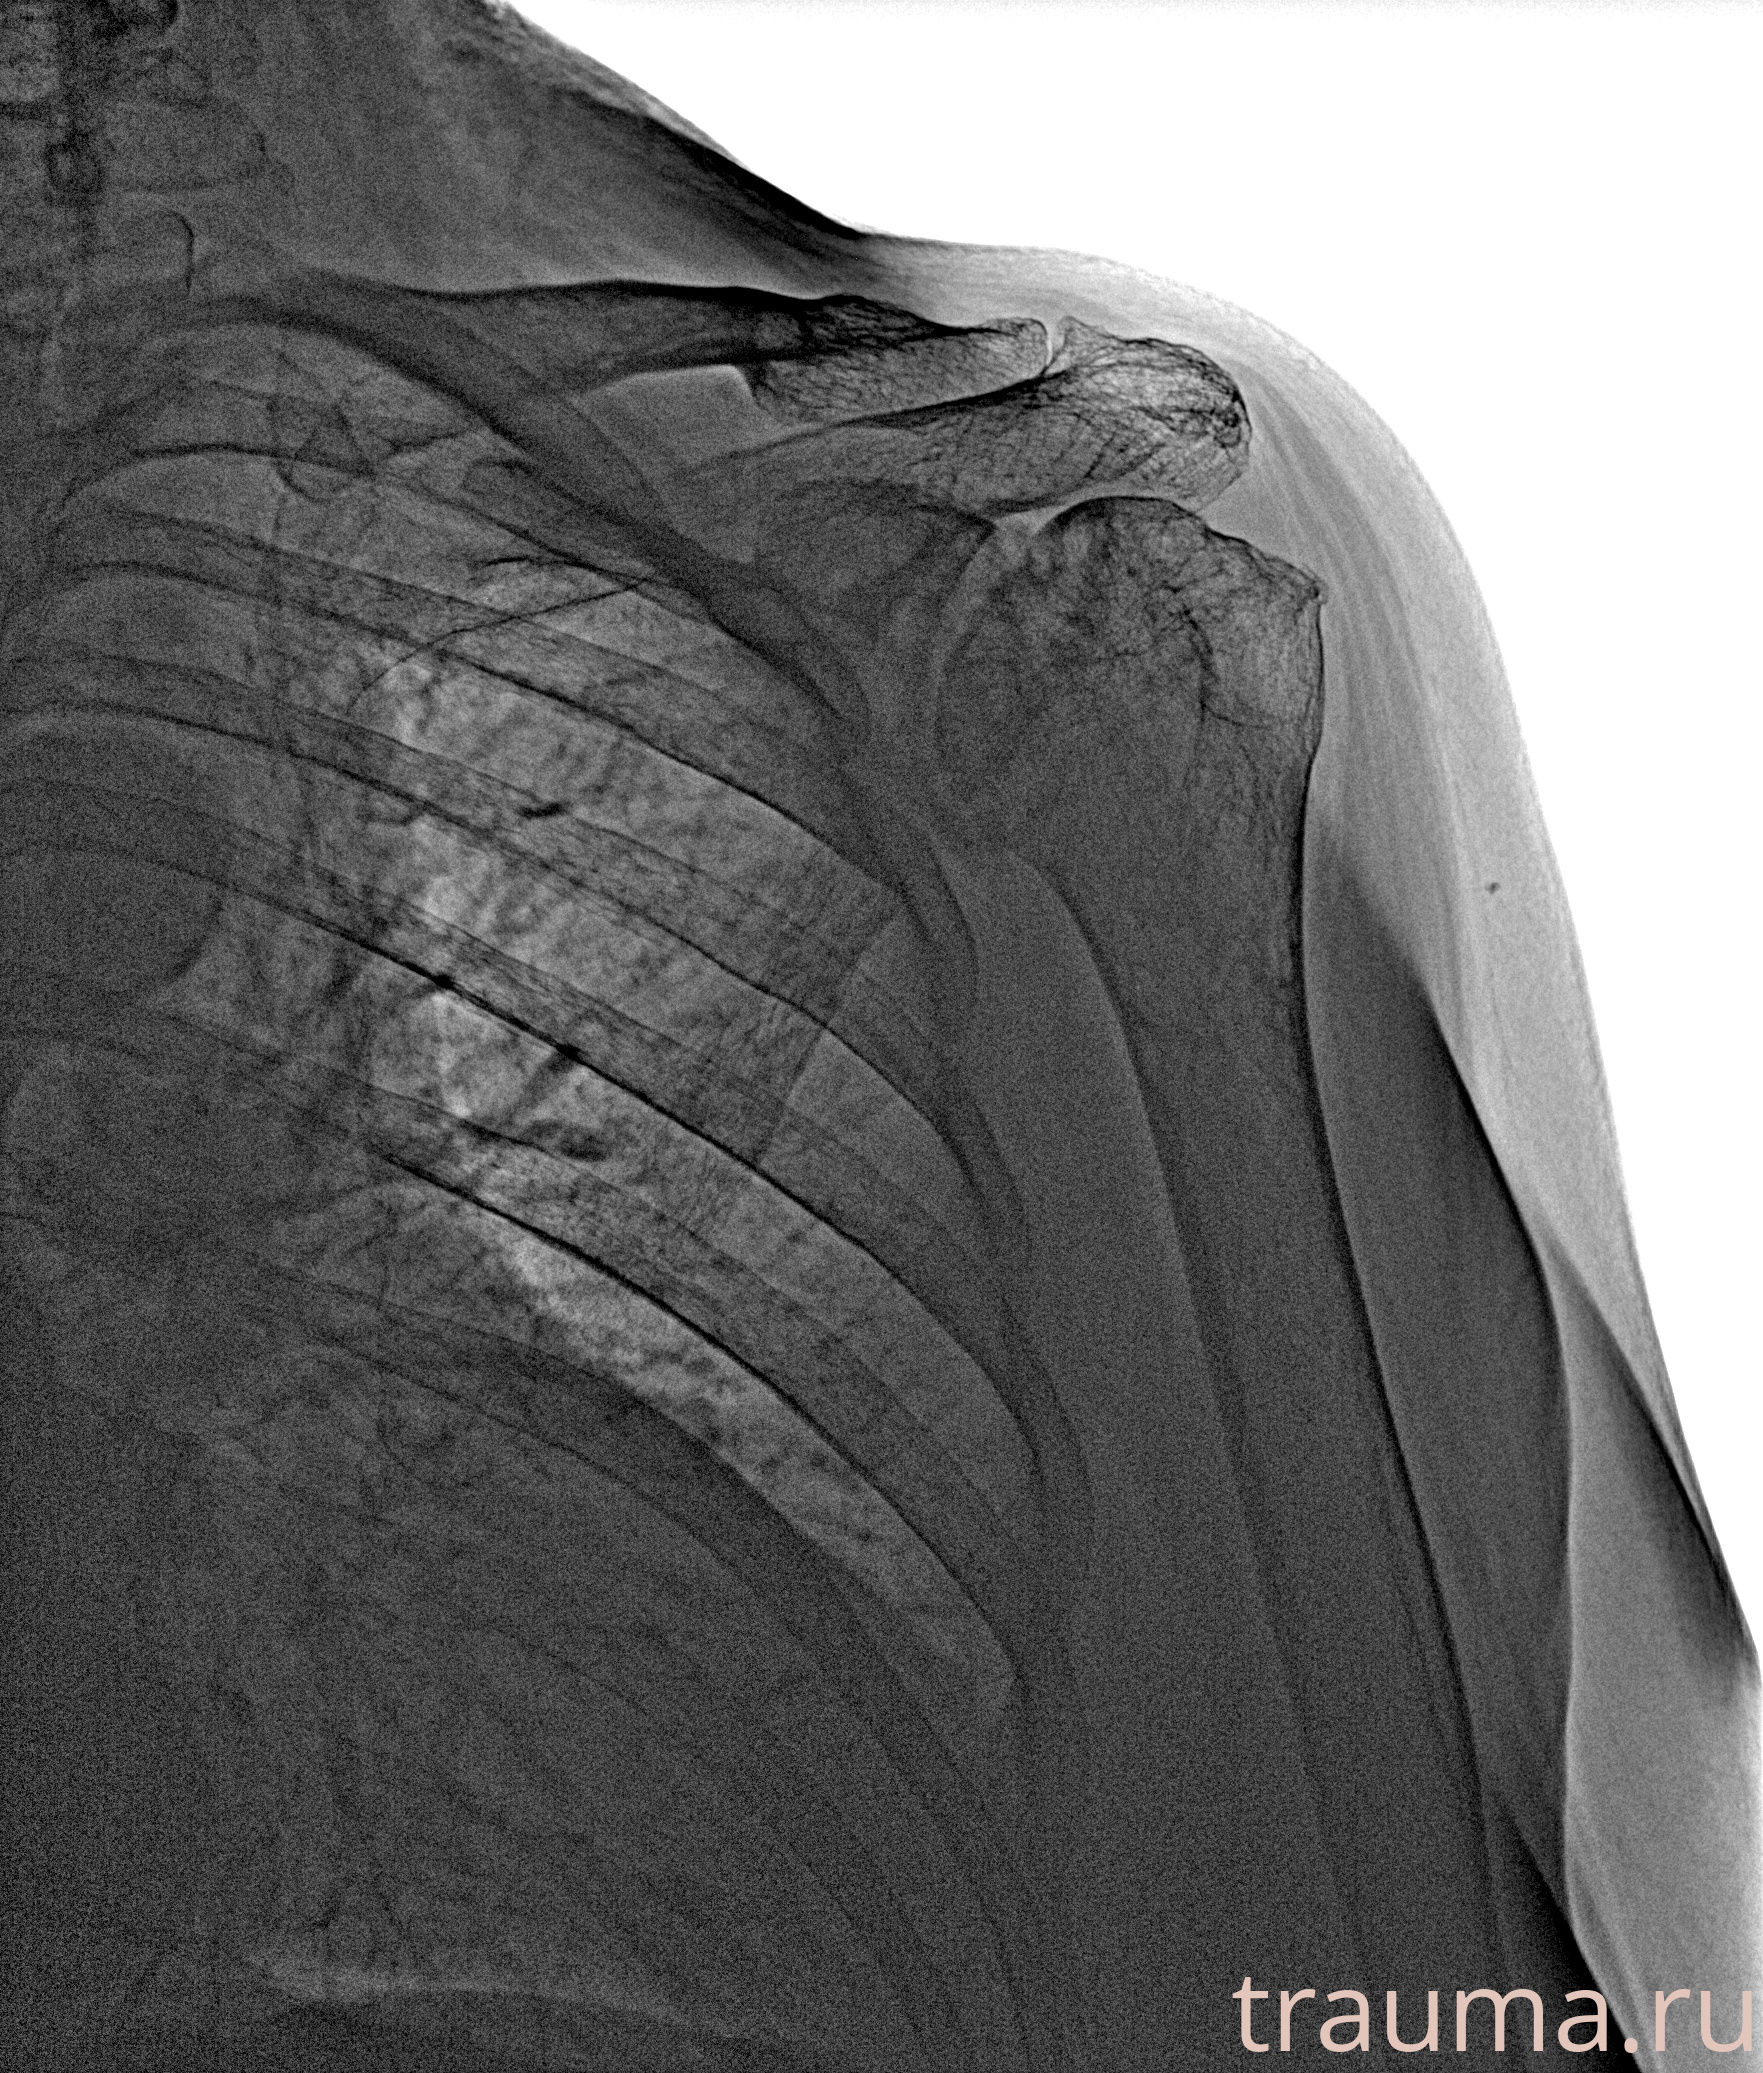

Рентген на дому: по вашему адресу приезжает врач-рентгенолог, травматолог-ортопед с мобильным рентгеновским аппаратом, проводит диагностику травмы или заболевания, делает необходимые рентгенограммы, дает рекомендации по дальнейшему лечению. Получить качественные снимки в домашних условиях возможно благодаря уникальной методике, разработанной МосРентген Центром для института  Склифосовского